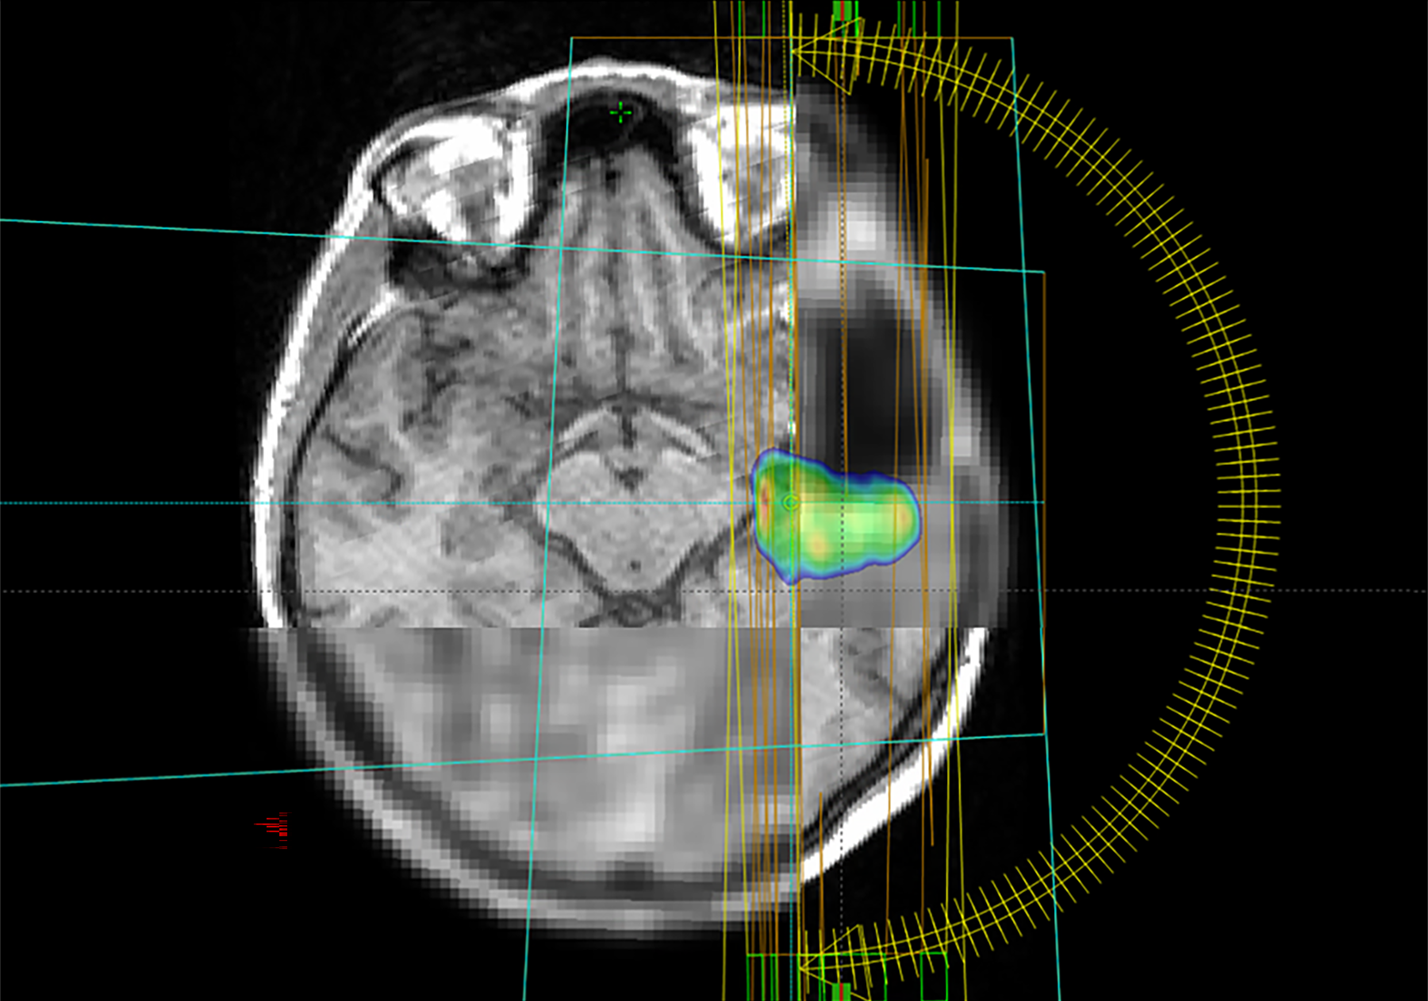

Glioblastome sind seltene, aber besonders aggressive Hirntumore. Häufig werden sie mit einer Strahlentherapie behandelt. Ein internationales Forschungsteam unter Leitung des Universitätsklinikums Freiburg untersucht nun in der Studie MATTO-GBM, wie der Tumor mit maximaler Intensität bestrahlt und umliegendes, gesundes Gewebe geschont werden kann. Dabei setzen die Forschenden auf eine erweiterte Bildgebung und eine Unterstützung durch Künstliche Intelligenz bei der Bildanalyse. Das Projekt wird von der Europäischen Union im Rahmen des Horizon 2020-Programms über drei Jahre mit 1,2 Millionen Euro gefördert.

Statt wie bisher meist nur Bilder aus dem Magnet-Resonanz-Tomografen (MRT) zu verwenden, nutzt das Forschungsteam aus Spanien, Deutschland und Österreich in der aktuellen Studie auch auf die Positronen-Emissions-Tomografie (PET)-Bildgebung. „Wie wollen durch die Kombination aus MRT und PET die biologischen Eigenschaften der Tumore besser verstehen. Damit wird der Stoffwechsel im Tumor sichtbar und eine hochwirksame Bestrahlung besonders gefährlicher Tumoranteile möglich“, sagt die Physikerin Monserrat Carles Fariña, die sowohl in Valencia, Spanien, als auch am Universitätsklinikum Freiburg im Projekt aktiv involviert ist.

Ein weiterer Fokus der Studie liegt auf dem Einsatz von Künstlicher Intelligenz: Sie hilft, den Tumor auf den Bildern genauer zu definieren und vorherzusagen, wann und wo er möglicherweise wieder auftreten könnte. Ein großes Ziel der Forscher*innen ist die Schaffung eines frei zugänglichen digitalen Tools. Dieses soll es Krankenhäusern weltweit ermöglichen, die Therapie des Glioblastoms auf das individuelle Risikomuster von einzelnen Patient*innen abzustimmen und so die Lebensqualität der Betroffenen zu erhöhen. Das Projekt bringt Spezialist*innen aus den Bereichen Künstliche Intelligenz, Radioonkologie, Nuklearmedizin, Neuroradiologie, Medizinphysik, Neuropathologie und Neurochirurgie zusammen.